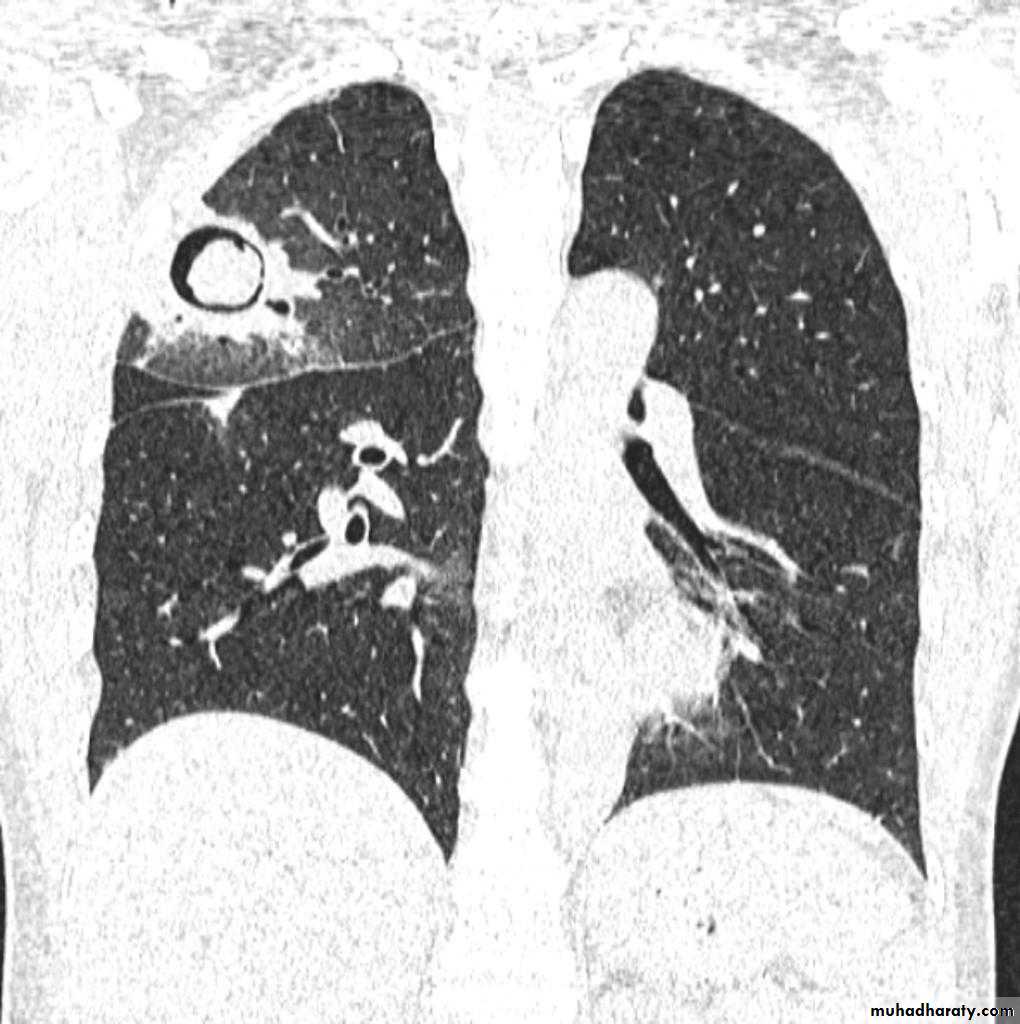

Plain film

The classical appearance of a pulmonary abscess is a cavity containing an air-fluid level. In general abscesses are round in shape, and appear similar in both frontal and lateral projections.

Very important

Empyema vs pulmonary abscess1.relationship to adjacent bronchi / vessels

abscesses will abruptly interrupt bronchovascular structures

empyema will usually distort and compress adjacent lung

2.split pleura sign thickening and separation of visceral and parietal pleura is a sign of empyema

3.abscesses have thick irregular walls

empyema are usually smoother

4.angle with pleura

abscesses usually have an acute angle (claw sign)

empyema have obtuse angles